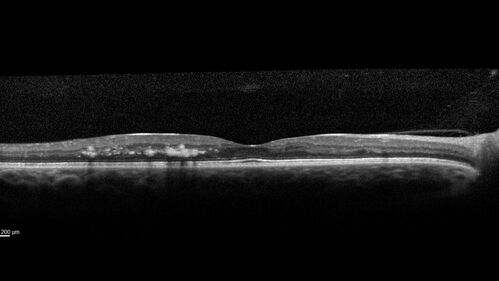

Macular ischemia left eye in type I diabetic (enlarged foveal avascular zone)

29 year old female with type I diabetes since age 5. Left eye has enlarged FAZ with vision of 20/20 OD and 20/60 OS. Both eyes have CSME. The left eye did have focal laser